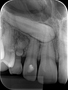

Radiografia Periapical